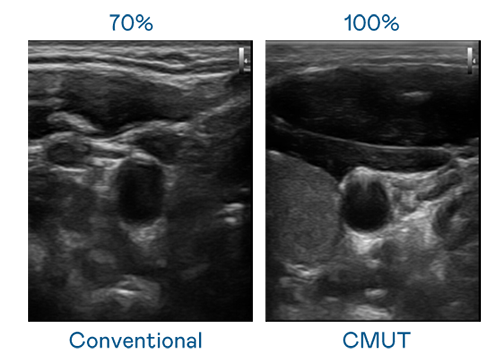

CMUT 技术是一种用电容式微机电元件来产生超音波讯号的技术。与传统 PZT 压电式技术相比,CMUT 频宽增加 30%,更宽频的超音波讯号让影像解析度大幅提升,是实现高影像品质医疗超音波扫描、促进精准医疗发展的关键技术。

超音波影像的解析度高低,首先取决于探头能发出的讯号频宽。爱游戏网页版官方入口 CMUT 可提供高清晰的超音波讯号,提供高频宽、高灵敏度、影像纹理细节更高的超音波影像,协助医护人员缩短影像判读时间及利用精准的医疗影像进行诊断。